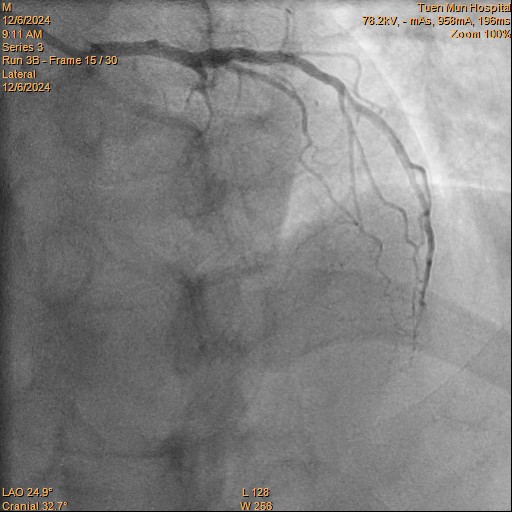

Relevant Catheterization Findings

LMS: Normal LAD: Occluded from proximal segment onwards, receiving collaterals from right system LCX: Moderate disease distally RCA: Dominant. Minor disease

cranial.avi